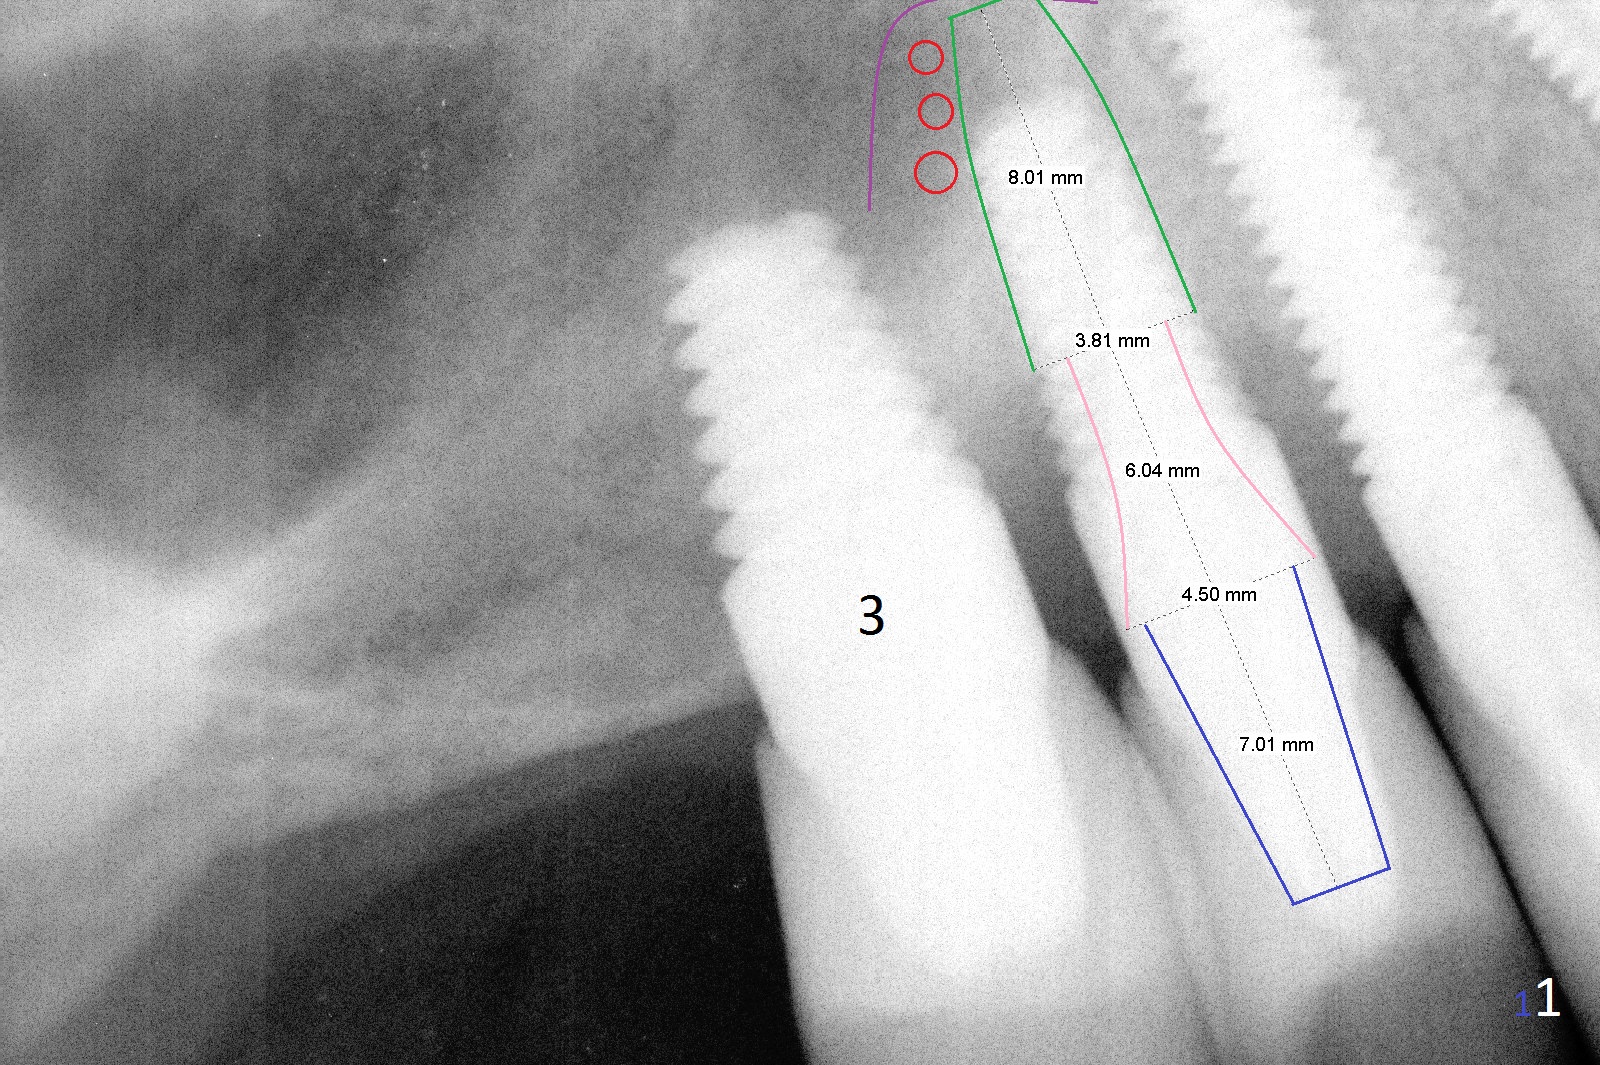

A 58-year-old man has two types of implant complications: periimplantitis at #4 (in spite of 2 bone graft surgeries, Fig.1) and abutment loosening at #14 and repeatedly 19 (probably due to bruxism, Fig.2,3).

For the implant #4 (4.5x14 mm), there are 2 options: exposed thread or implant removal. Either way, make an ample incision. Prepare long diamond burs. Soak several pieces of gauze in 1:1000 Epinephrine. The implant will be removed using 5/6 mm trephine bur or surgical handpiece, followed by immediate placement of a bone-level implant with the longest abutment cuff (Fig.1: 6 mm (pink)). Insert PRF (purple line, 4-5 tubes of blood) and allograft (red circles) prior to implantation. The implant/crown ratio is poor, place a long healing abutment or cemented abutment with the shortest abutment height (4 mm vs. 7 mm of the final one (Fig.1 blue, 6-8 months of healing)). If the site is unfavorable for implantation, a 3-unit bridge will be fabricated.